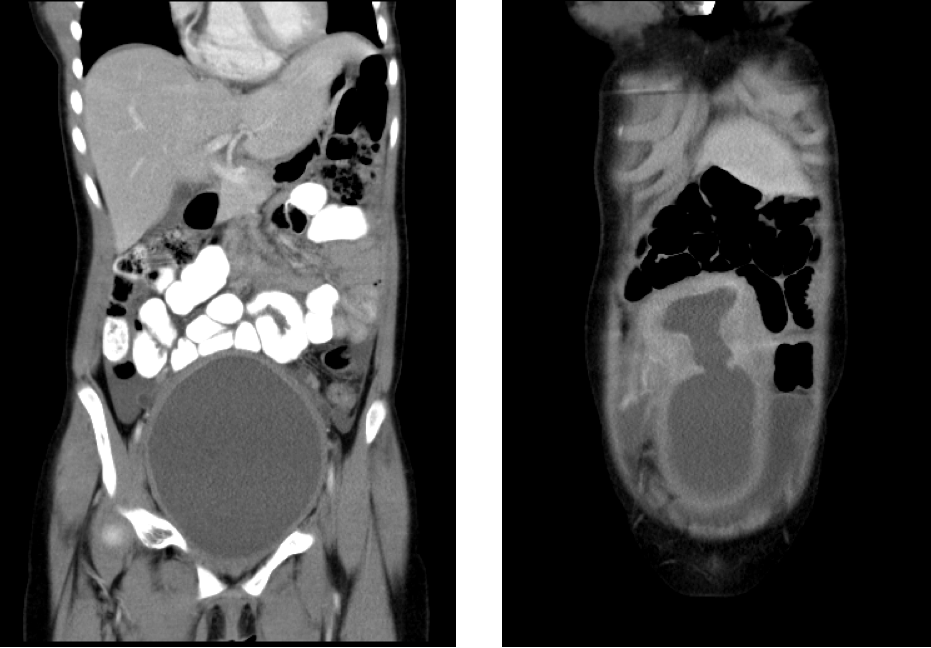

長了胸部,怎麼月經遲遲不來?一名13歲少女因為腹脹半年,被媽媽帶到小兒科求診,檢查赫然發現,少女是罕見的處女膜閉鎖加上陰道橫膈,造成子宮陰道積血,經超音波導引下將陰道橫膈打開,這才順利排出經血約1200cc之多。

三軍總醫院小兒外科主治醫師林介文表示,一開始的影像檢查發現少女有子宮陰道積血的狀況,即高度懷疑是處女膜閉鎖造成的陰道出口阻塞,但手術將處女膜切開後,卻未看見經血流出,進一步由婦產科醫師以手指內診才發現有上陰道橫膈。